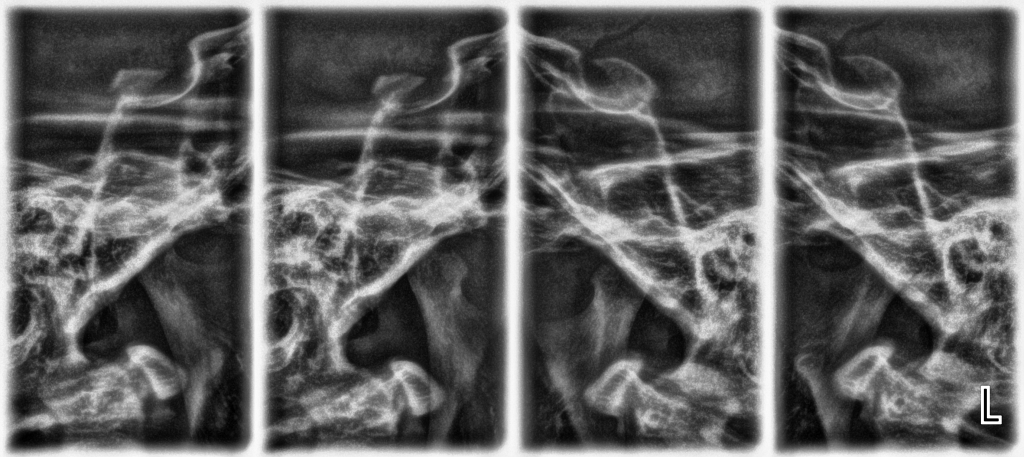

С този вид рентгеновата снимка се визуализират двете темпоромандибуларни стави – лява и дясна, чрез които долната челюст е подвижно свързана с основата на черепа, като дава възможност за сравнението им при отворена и затворена уста. Необходима е за диагностициране на проблеми в ТМС и тяхното лечение.